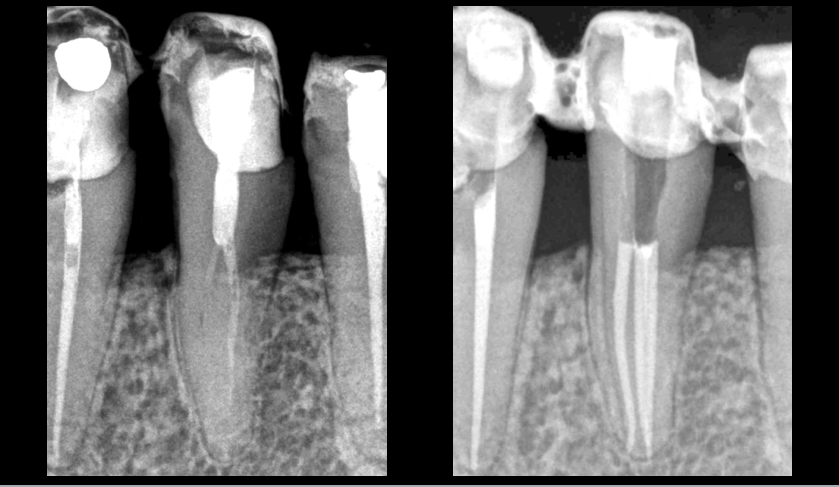

✅ 𝐔𝐧𝐞 𝐨𝐛𝐭𝐮𝐫𝐚𝐭𝐢𝐨𝐧 𝐦𝐨𝐧𝐨𝐜𝐨𝐧𝐞 𝐚̀ 𝐟𝐫𝐨𝐢𝐝 (ciment à base de silicate : Bioroot RCS)

✅ 𝐔𝐧𝐞 𝐨𝐛𝐭𝐮𝐫𝐚𝐭𝐢𝐨𝐧 𝐯𝐞𝐫𝐭𝐢𝐜𝐚𝐥𝐞 𝐚̀ 𝐜𝐡𝐚𝐮𝐝 (ciment oxyde de zinc eugénol : Pulp Canal Sealer EWT)

📌 𝐂𝐞𝐜𝐢 𝐚̀ 𝟒 𝐚𝐧𝐬, d’après :

📍 𝐔𝐧 𝐞𝐬𝐬𝐚𝐢 𝐜𝐥𝐢𝐧𝐢𝐪𝐮𝐞 𝐫𝐚𝐧𝐝𝐨𝐦𝐢𝐬𝐞́

📍 𝐄𝐟𝐟𝐞𝐜𝐭𝐮𝐞́ 𝐬𝐮𝐫 𝟗𝟐 𝐝𝐞𝐧𝐭𝐬

📖 𝐁𝐚𝐫𝐝𝐢𝐧𝐢, 𝐆., 𝐁𝐞𝐥𝐥𝐢𝐝𝐨, 𝐌. 𝐌., 𝐑𝐨𝐬𝐬𝐢‐𝐅𝐞𝐝𝐞𝐥𝐞, 𝐆., 𝐂𝐚𝐬𝐮𝐥𝐚, 𝐋., 𝐃𝐞𝐭𝐭𝐨𝐫𝐢, 𝐂., 𝐈𝐝𝐞𝐨, 𝐅., & 𝐂𝐨𝐭𝐭𝐢, 𝐄. (𝟐𝟎𝟐𝟓). A 4‐year follow‐up of root canal obturation using a calcium silicate‐based sealer and a zinc oxide‐eugenol sealer: A randomized clinical trial. International Endodontic Journal, 58(2), 193-208.